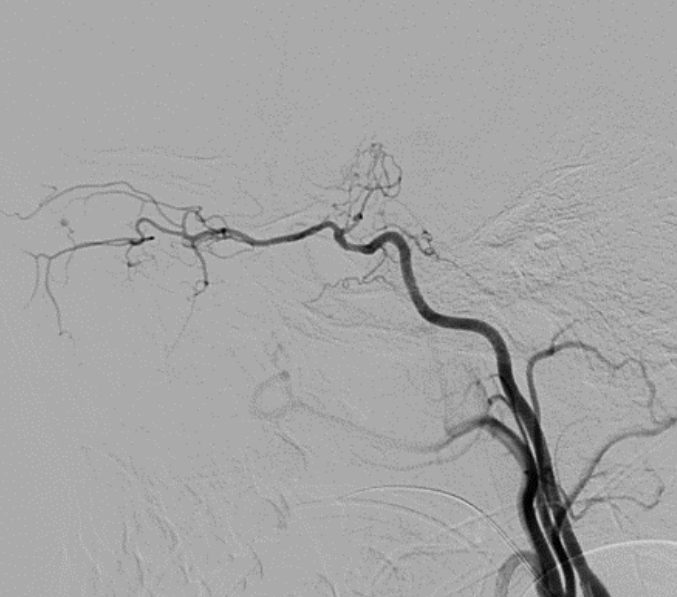

烟雾病(Moyamoya)是颈内动脉的慢性进行性脑血管闭塞性疾病,与大脑底部获得性异常血管网络有关,通常导致缺血性或出血性中风...

烟雾病是一种进展性狭窄闭塞性大血管脑动脉病,可导致缺血性中风,常见于儿童,也可见于出血性中风,见于成人...